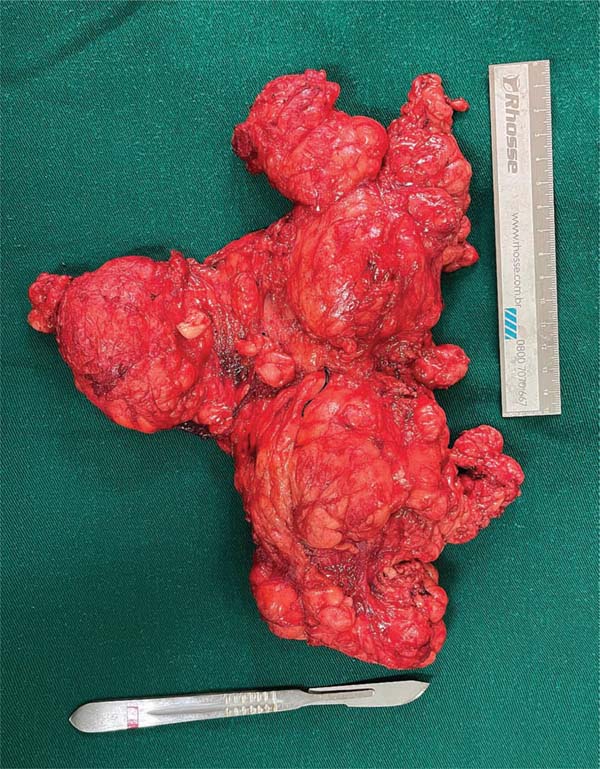

Após a internação hospitalar e as avaliações pré-operató-rias, a equipe de Cirurgia Plástica optou pela ressecção seriada das lesões (►Figs. 2-3), com a incorporação de dermolipectomias e uso de retalhos locais para reconstru-ções. O tratamento foi inicialmente centrado na região cervical, onde o paciente sentia maior desconforto. A cirurgia envolveu a ressecção de uma massa superficial ao platisma, que havia infiltrado parcialmente as glândulas parótidas, em especial a esquerda. O nervo hipoglosso foi preservado durante a dissecção da glândula submandibular, enquanto o nervo mandibular marginal foi protegido por meio de uma dissecção meticulosa dos polos inferiores das glândulas parótidas, guiada por seu trajeto anatômico conhecido. Esse processo foi auxiliado pelo monitoramento intraoperatório dos nervos, que permitiu a identificação e o mapeamento precisos da trajetória do nervo, garantindo sua preservação em toda a sua extensão.